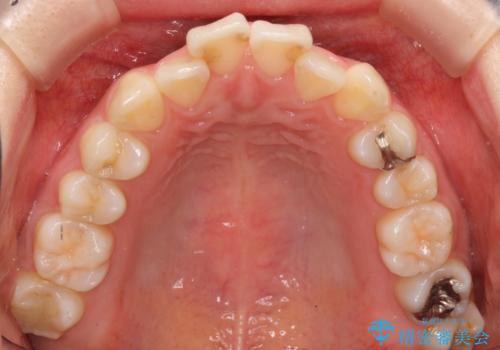

軽度の前歯のがたつき 下の前歯が生まれつき少ない

- 前歯のがたつきを主訴に来院。

下の前歯が生まれつき3本でした。

そのため、上の前歯が少し余るような形で出っ歯になっていたため、スペースを作って引っ込めています。

下を3本でそのまま並べてあるため、上下の正中は合いません。

合わせようとすると抜歯か、下の隙間を無理やり開けてブリッジとなりますが、そこまでするメリットがないため、下はそのままの歯の数を生かしています。